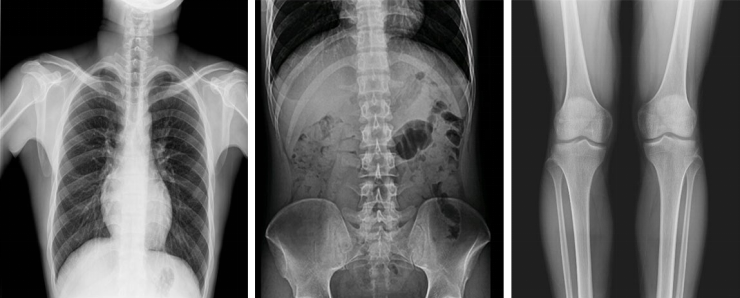

不同于常規(guī)靜態(tài)DR只能進行平片攝影檢查,動態(tài)DR可以滿足多種臨床檢查需求,包括靜態(tài)檢查、透視檢查、造影檢查、脊柱及下肢全長拼接檢查,相較于靜態(tài)DR具有豐富的臨床應(yīng)用,且動態(tài)DR檢查更精準(zhǔn)、直觀,擺位攝片效率極大地提升,大大節(jié)省拍片時間。

動態(tài)DR影像采集幅面大,17×17英寸超大視野,可覆蓋成年人的全胸全腹,并且能在連續(xù)動態(tài)中實時高清點片,還可以進行視頻保存,在會診過程中可以回放影像檢查視頻,從而達到精準(zhǔn)診斷的目的。同時動態(tài)DR還具有全身拼接功能,尤其適用于全脊柱和全下肢攝影,輔助脊柱畸形矯形治療、康復(fù)檢查,為臨床提供高精度圖像。